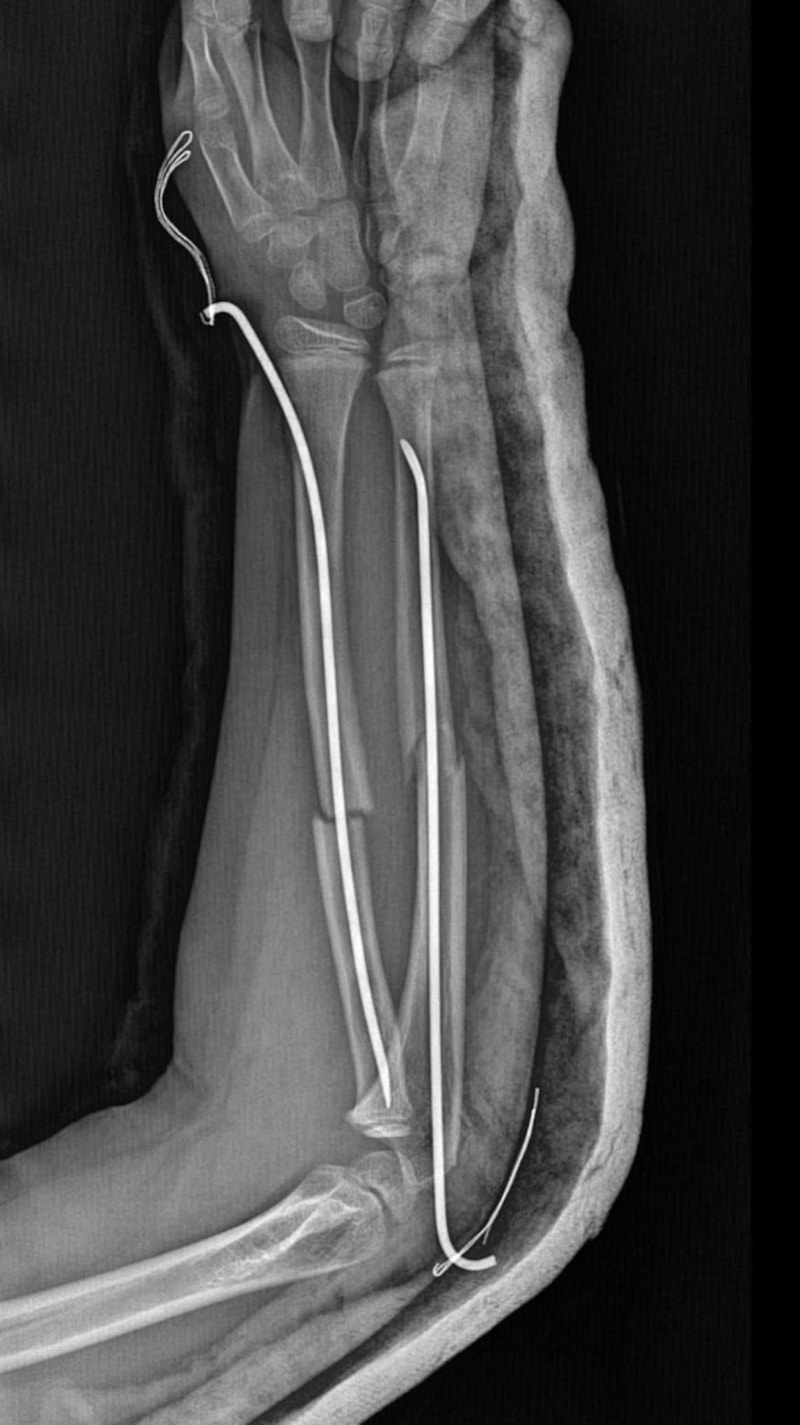

İstanbul Büyükçekmece Tepecik'te bulunan bir ilkokulda 8 yaşındaki Y.K.Ş., okulda bir süredir kendisini rahatsız eden 9 yaşındaki çocuk tarafından darbedilerek, kolu ikiye katlandı.

Y.K.Ş.'nin ikiye katlanan kolu, 2 ayrı yerinden kırıldı.

Oğlunu okuldan alıp hastaneye götüren anne Songül Gökdemir, oğlunun kolunun 2 ayrı yerinden kırıldığını öğrenip, ameliyata alınacağını duyduğunda büyük şok yaşadı.

Anne Gökdemir karara itiraz ederken mağdur Y.K.Ş. ise haftalardır okula gidemiyor. Eğitimi aksayan çocuğun, 2 hafta sonra ise platinlerinin çıkarılması için yeniden ameliyata gireceği öğrenildi.

3 gün sonra ameliyata alındı. Kolundaki platinlerden dolayı her gün pansumanı var. 2 hafta sonra tekrar ameliyatı var." dedi.